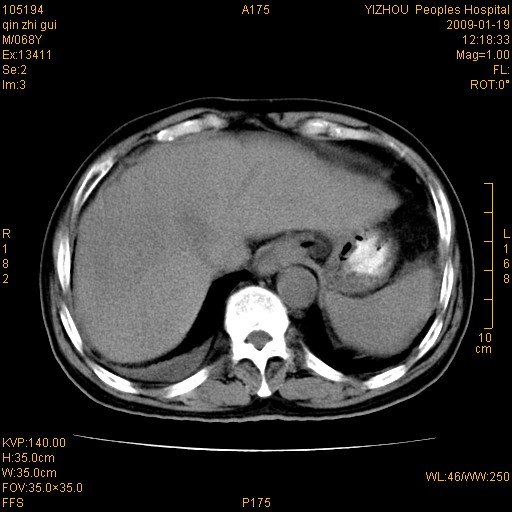

以下是引用随光逐影在2009-1-21 16:11:00的发言:[br]1)考虑肝右叶肝癌并肝静脉及门静脉瘤栓形成。2)肝硬化,少量腹水。3)胆囊炎。4)右侧少量胸腔积液。

病灶外缘凹凸不平,平扫低密度,增强动脉期有强化,门脉早显,静脉期及延期呈延迟强化,结合病史考虑右肝前叶巨块型肝癌可能性大,强化表现不除外胆管细胞癌